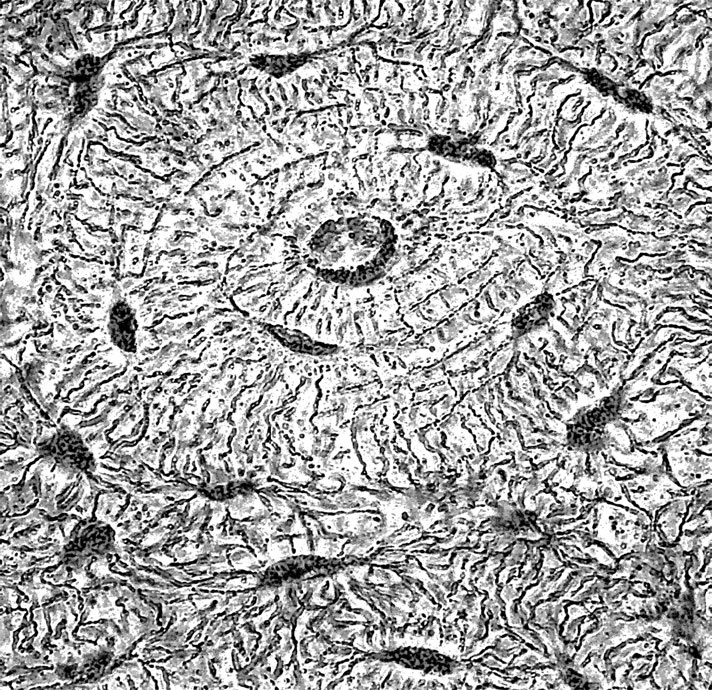

Мерцательный эпителий

Кроме перечисленных функций, эпителиальная ткань может участвовать во всасывании веществ (эпителий кишечника) и в газообмене (эпителий легких). Дыхательные пути выстланы особым видом эпителиальной ткани, называемой «мерцательным эпителием», клетки которого имеют обращенные наружу подвижные реснички. Эти реснички удаляют из дыхательных путей мелкие твердые частицы, попадающие туда с воздухом.